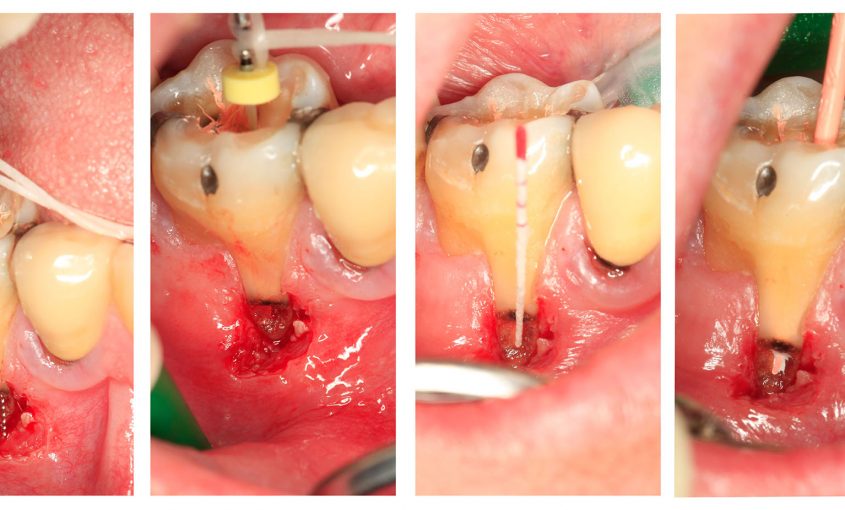

Cada vez con más frecuencia, los pacientes acuden a la consulta del dentista demandando soluciones altamente estéticas. La prótesis totalmente cerámica o con estructuras de circonio suele ser uno de los tratamientos más utilizados para resolver con éxito este tipo de situaciones. En algunos casos, una vez cementada la prótesis, acontece un problema de tipo